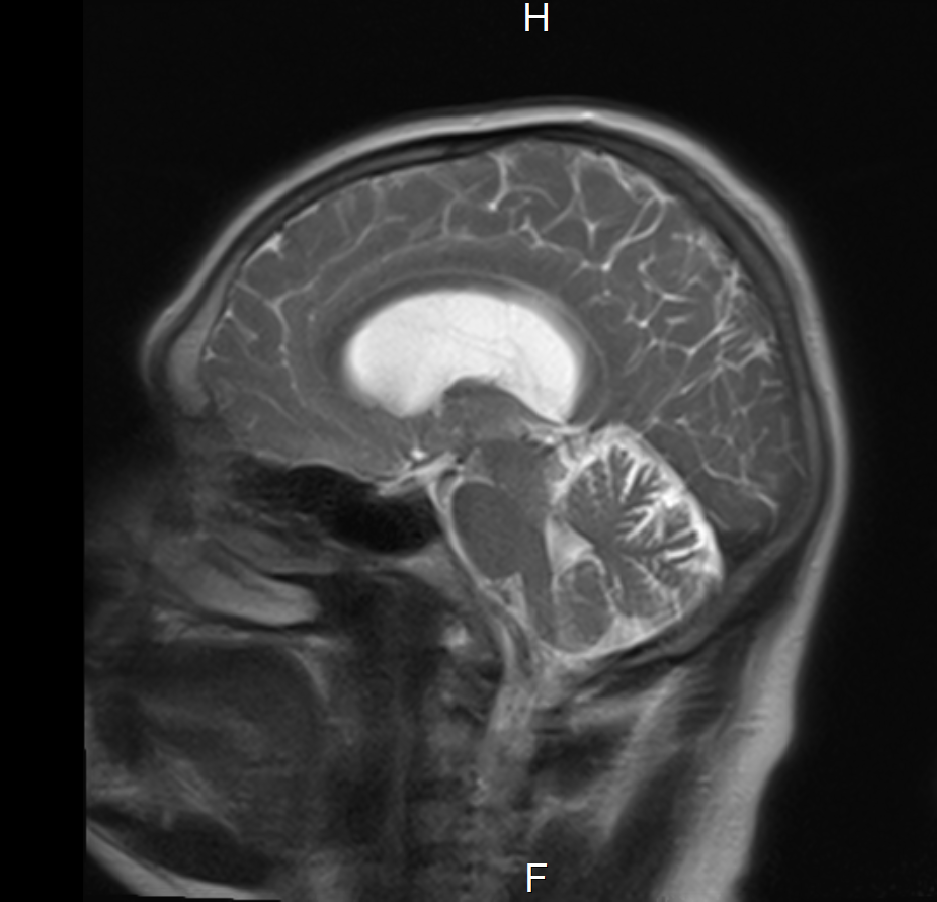

I shared the picture above at the Digital Health Rewired conference a couple of years ago. I know what you’re thinking: it’s a head. It’s a brain. With a bright point that shouldn’t be there. In fact, it’s my head, and my brain, and the bright spot is a colloid cyst.

A colloid cyst called Liszt

This benign brain tumour, which I call Liszt, was discovered a few years ago as an incidental finding on an MRI scan. It has very little impact on my life, but that could change. So, I need an annual check-up with a consultant, and there are some symptoms that I need to look out for, like forgetfulness, dizzy spells, headaches, and slurred speech.

There’s no reason to think Liszt will ever be anything more than an interesting spot on a scan. Something to pop onto a PowerPoint, to show how ICE and ICE OpenNet have transformed the process of ordering, reporting and sharing tests. And to show how creative use of the ICE Diagnostic Hub could transform healthcare further still.